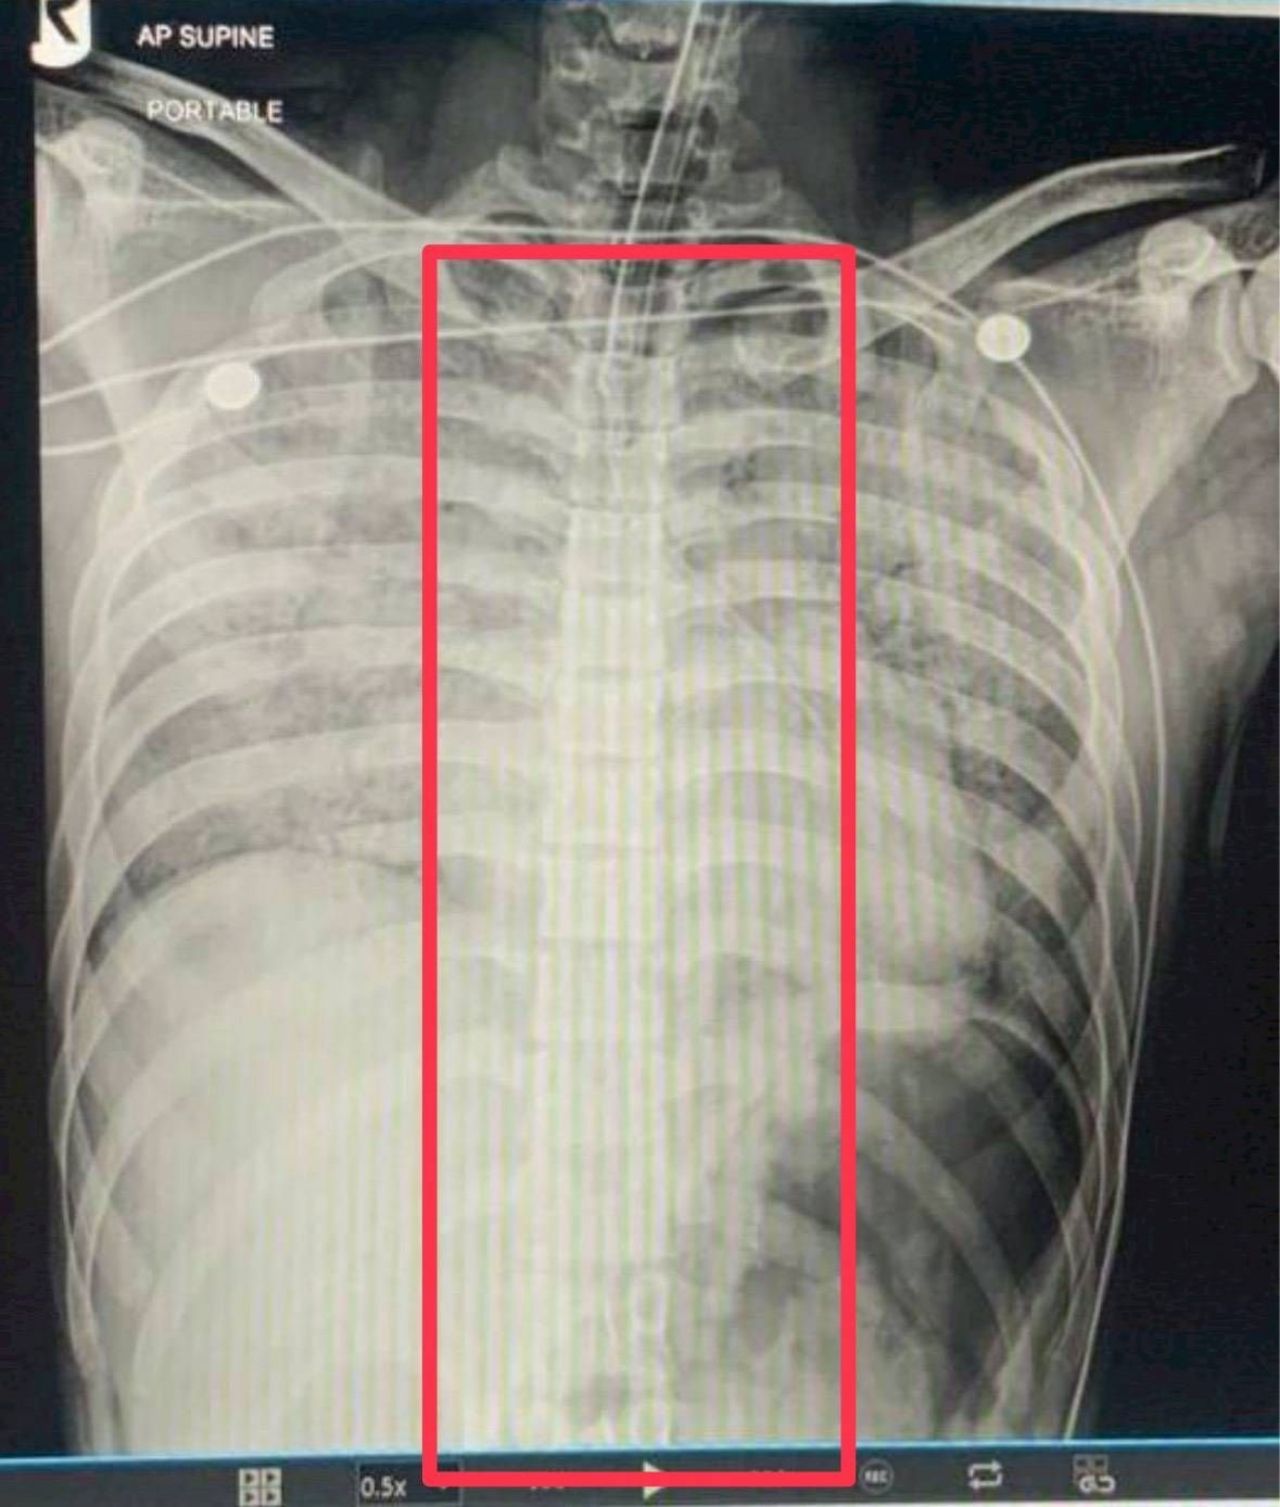

โดยส่วนตัวผมไม่ทราบว่า ช้อนมาได้ยังไง เท่าที่ทราบจากการผ่าพิสูจน์จะมีฟิล์มเอกซเรย์ของทางโรงพยาบาล ไม่ปรากฏ “ช้อน” อยู่ในร่างกายของผู้เสียชีวิต และมีการนัดหมายกับทางญาติ และหน่วยงานที่เกี่ยวข้อง นำรูปถ่ายและคลิปต่างๆ ให้ญาติดู และเดินเข้าไปดูด้านใน ซึ่งขณะนั้นญาติไม่ติดใจอะไร เข้าใจว่าน้องเสียชีวิตด้วยโรคส่วนตัว